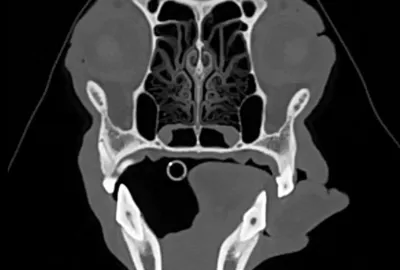

Hlava a krk:

Zobrazení a diagnostika patologií v dutině nosní (nádory, chronické záněty, cizí tělesa). Zlomeniny čelistí. Hluboké procesy v nosohltanu a krku (nasopharyngeální abscesy). Patologie v oblasti oka. Některé nádorové procesy mozku a lebky. Fraktury lebky, krvácení do mozku. Poranění krční páteře. Poranění dýchací trubice či hrtanu.